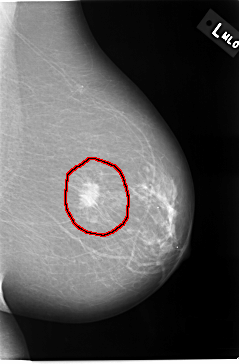

C_0037_1.LEFT_MLO

LEFT_MLO LINES 5816 PIXELS_PER_LINE 3824 BITS_PER_PIXEL 12 RESOLUTION 50 OVERLAY

FILE: C_0037_1.LEFT_MLO.OVERLAY

TOTAL_ABNORMALITIES 1

ABNORMALITY 1

LESION_TYPE MASS SHAPE IRREGULAR MARGINS SPICULATED

ASSESSMENT 5

SUBTLETY 5

PATHOLOGY MALIGNANT

TOTAL_OUTLINES 1

BOUNDARY